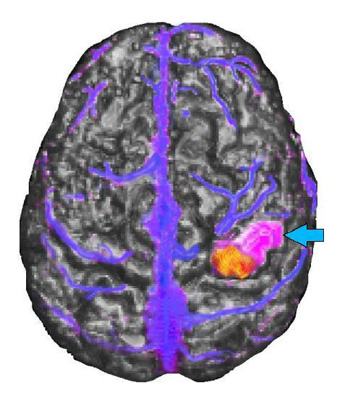

Caso 2

Niña diestra de 15 años de edad con convulsiones sensoriales motoras parciales que involucran la mano izquierda desde los 5 años de edad. La IRM mostró una anomalía de señal focal en la circunvolución postcentral derecha como consecuencia de un tumor en desarrollo sin cambios durante un período de 2 años.

Vista de representación triple sagital media superior

La IRM del cerebro aparece en una escala de grises, la activación por RM funcional se muestra en amarillo y rojo, el tumor se ve de color púrpura (flecha celeste) y las venas, de color azul. El tumor aparece localizado en la circunvolución postcentral de forma lateral y rostral con respecto a la activación funcional. La relación entre el tumor y la activación funcional fue confirmada durante el mapeo intraoperativo con el paciente despierto. Los puntos de referencia venosos proporcionaron información útil al cirujano que realiza la intervención. Se extirpó el tumor de la paciente sin monoplejia residual. La paciente solo presentó pérdida temporal de estereognosis y propiocepción relacionada con el tercer, cuarto y quinto dedo, después de la cirugía.